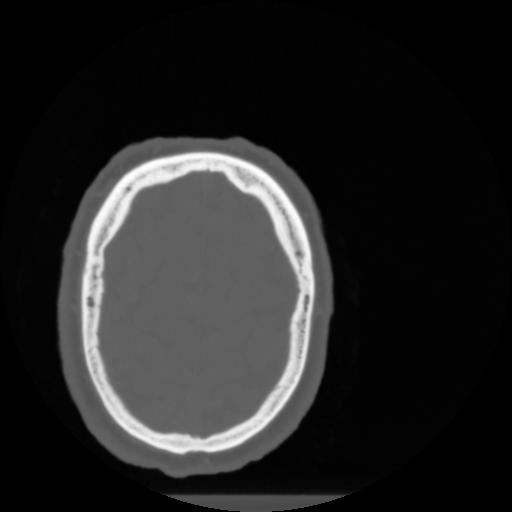

4 CEREBRO,,Vol,0.5,CEREBRO,,